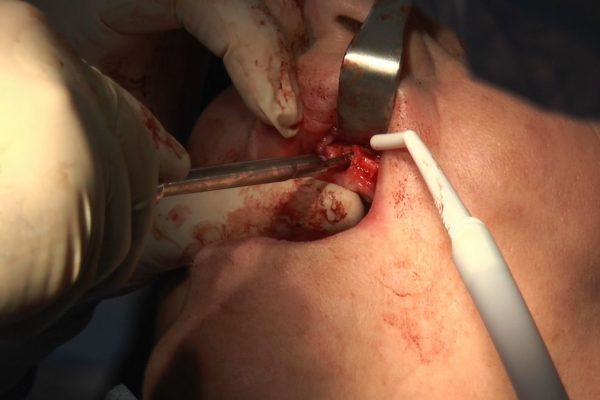

W ostatni weekend czerwca 2018 roku kursanci II Sezonu Preludium Implantologii odbyli piątą, finałową sesję, która w całości podporządkowana była praktyce. W ciągu dwóch dni zabiegowych Lekarze uczestniczący w szkoleniu przeprowadzili szereg zabiegów pod kierunkiem dr n.med. Violetty Szycik. Wszczepili 17 implantów oraz przeprowadzili ekstrakcje i zabiegi regeneracyjne kości. Zabiegi były wykonywane także w sedacji dożylnej z udziałem specjalisty anestezjologii i intensywnej terapii dr Jolanty Grzybowskiej. Preludium implantologii to nowy program edukacyjny dla adeptów implantologii stomatologicznej, którego celem jest wprowadzenie do implantologii poprzez pozyskanie wiedzy w szerokim zakresie i uwzględnieniem szczegółów mających decydujące znaczenie dla powodzenia leczenia implantologicznego. Ale tak jak wszystkie szkolenia w Instytucie Vivadental, w tym wiodące Practiculum Implantologii, zorientowane jest na praktyce i samodzielnym wykonywaniu zabiegów pod kierunkiem Mentora. To najlepsza edukacja w medycynie zabiegowej, a zarazem najlepszy start do implantologii.